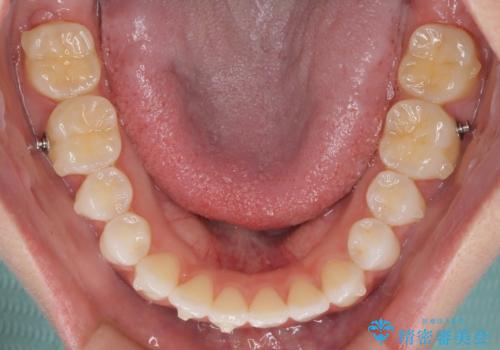

前歯のオープンバイトを治したい インビザラインでの矯正治療

- インビザライン

- 前歯の上下スペースによる話しにくさと顎への負担を気にして来院された患者様です。

インビザラインにより上顎の大臼歯を圧下し、上下の前歯の隙間を閉じていくこととしました。

上顎の奥歯を圧下させることで、上下前歯を接触させるように計画しました。

前歯が急に接触するようになり、慣れるまで時間がかかりましたが、前歯でものが咬めるようにもなり、患者様には大変満足していただきました。